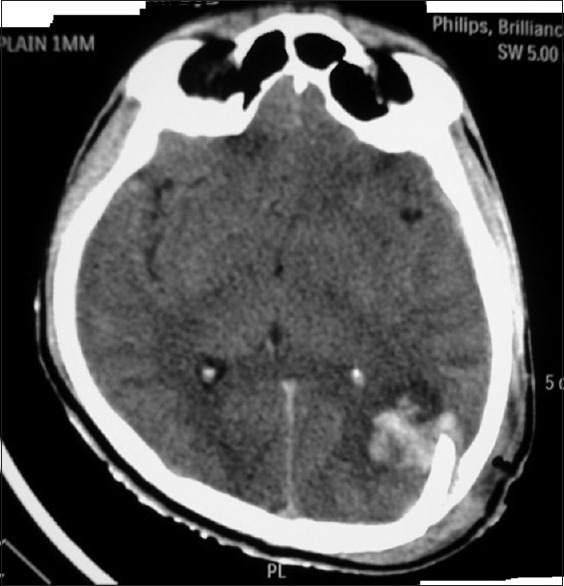

A 26-year-old male with depressed fracture in the left posterior parietal bone presented to us with overlying contused lacerated wound and contamination of the wound. GCS was 14/15 and with disoriented speech. CT revealed underlying contusion in the left posterior parietal region [Figure 4]. The patient was operated, and the depressed segment was excised (due to contamination) with the dural repair. Postoperative CT showed resolution of contusion with postoperative bony defect [Figure 5].

Figure 4.

Axial plain computerized tomography image showing postoperative changes with resolution of contusion

Figure 5.

Axial plain computerized tomography image showing depressed fracture in left posterior parietal bone with underlying contusion